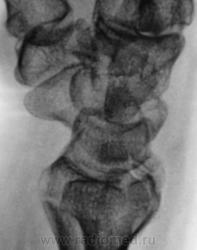

Пациент направлен на рентгенографию лучезапястного сустава.

Пациент направлен на рентгенографию лучезапястного сустава хирургом, была травма. После производства снимков стали допытываться у пациента, о "факте более ранней травмы". Все бесполезно - не помнит, не знает ....

Ваше мнение, уважаемые коллеги?